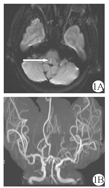

例1女,68岁,既往有高血压病史,平素口服氨氯地平片(5 mg/次,1次/d)及坎地沙坦酯(8 mg/次,1次/d)降血压治疗,未监测血压。患者因"头晕伴恶心6 h"入院。6 h前与他人争吵后出现头晕、视物旋转、行走不稳伴恶心、呕吐。无视物不清以及复视,无言语不清及饮水呛咳,无吞咽困难,无肢体麻木无力,无意识障碍及肢体抽搐。入院查体:双肺呼吸音清,未闻及干湿性啰音;心率78次/min,律齐,心脏各瓣膜听诊区未闻及杂音;腹软,无压痛及反跳痛;双下肢无水肿。神经系统查体:意识清楚,言语流利。双侧瞳孔等大同圆,光反应灵敏;双眼可见水平向右眼震,水平头脉冲试验(horizontal head impulse test,h-HIT)向左阳性,凝视诱发眼震阴性。四肢肌力5级,肌张力正常。共济运动完成好;双侧病理征阴性。深浅感觉无异常。入院后行头颅磁共振检查示脑干梗死(图1)。给予口服阿司匹林肠溶片(100 mg/次,1次/d)抗血小板聚集、阿托伐他汀钙片(20 mg/次,1次/d)调节血脂;静脉滴注银杏叶提取物注射液70 mg+ 0.9%氯化钠注射液250 ml(1次/d)改善循环等治疗。患者症状好转后出院。嘱继续行脑梗死二级预防治疗。

注:1A:DWI示内侧纵束高信号,提示内侧纵束梗死;1B:脑血管成像示轻度脑动脉硬化